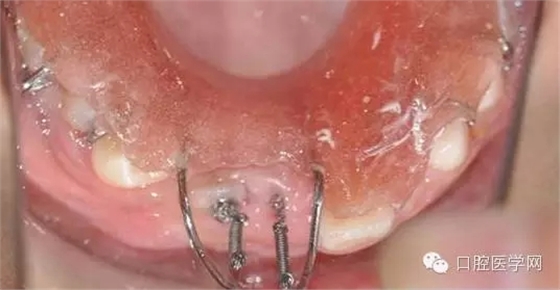

光固化型正畸粘結劑粘結鏈式牽引裝置

鏈狀正畸牽引裝置粘固后的口內情況

這個鏈式的超級好用,大力推薦。質量很好避免了結扎絲容易斷,托槽粘結不牢的弊端。(寫到這個地方不得不聊個小橋段,上次去上海咱會淘到的這個鏈式固定裝置,本來小美女說是40元一個,結果我說俺常做埋伏牙,要給人家做做宣傳,10元一個就給我試用了。40元給我4個,當時那叫一個感動呀,。。感謝生命中遇見了你。。。